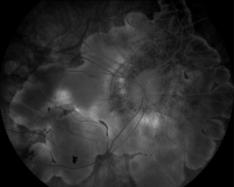

IM000038.JPG